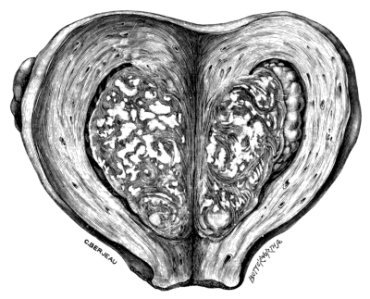

| 4. | A Tuberculous Fallopian Tube and Ovary: Entire and in Section | 24 |

| 5. | Primary Cancer of the Fallopian Tube | 27 |

| 6. | A Section of Primary Cancer of the Fallopian Tube | 27 |